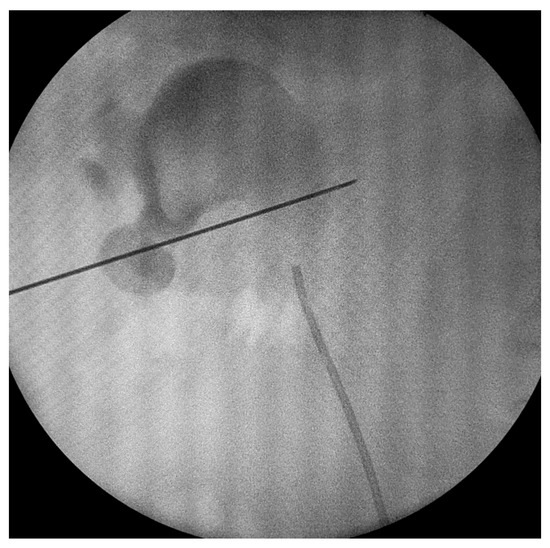

After that, a 0.035-inch hydrophilic guide wire was inserted into the collecting system. Dilation was performed using Amplatz dilators, and a 16 Fr Amplatz sheath was inserted. We used a 15.9 F rigid nephroscope and stone fragmentation was performed using Ho-YaG laser lithotripsy (350 or 550 μm fiber), ballistic energy or combined ultrasonic and ballistic lithotripsy (Figure 1 and Figure 2). Stone fragments were removed in the next step using the so called “vacuum effect” or using grasping forceps. The “vacuum effect” is based on a hydro-dynamic phenomenon which takes place during low-pressure, continuous-flow PCNL. Stone fragments located in line with the irrigation channel of the nephroscope were washed by the flow of water [10,11]. Some fragments were not removed with this technique so they needed extraction using a 1.9 F stone basket or tri-radiate graspers. After all fragments were removed, the collecting system was inspected visually and then evaluated with a contrast medium, under fluoroscopy, in order to identify residual stones and fragments or perforations.

Figure 2. Percutaneous renal access.